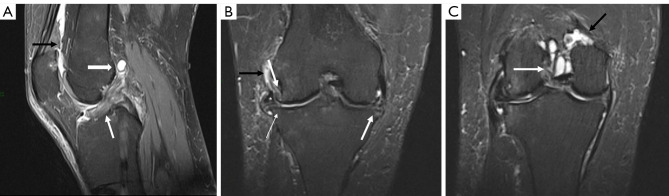

Abstract Image